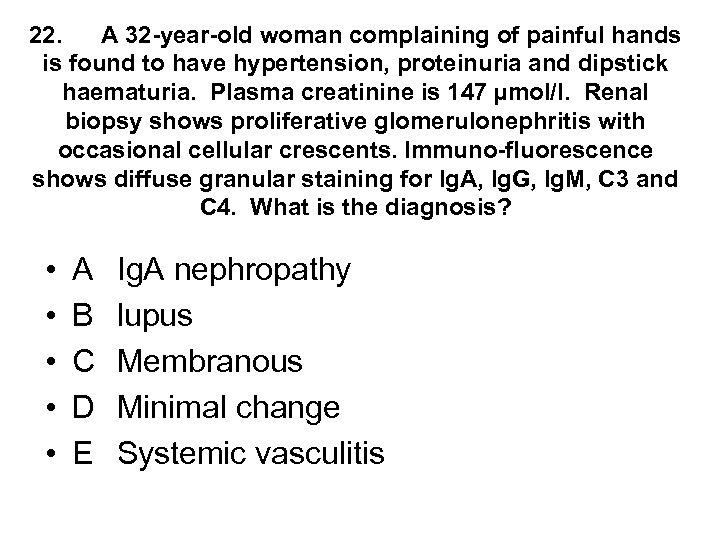

22. A 32 -year-old woman complaining of painful hands is found to have hypertension, proteinuria and dipstick haematuria. Plasma creatinine is 147 µmol/l. Renal biopsy shows proliferative glomerulonephritis with occasional cellular crescents. Immuno-fluorescence shows diffuse granular staining for Ig. A, Ig. G, Ig. M, C 3 and C 4. What is the diagnosis? • • • A B C D E Ig. A nephropathy lupus Membranous Minimal change Systemic vasculitis

22. A 32 -year-old woman complaining of painful hands is found to have hypertension, proteinuria and dipstick haematuria. Plasma creatinine is 147 µmol/l. Renal biopsy shows proliferative glomerulonephritis with occasional cellular crescents. Immuno-fluorescence shows diffuse granular staining for Ig. A, Ig. G, Ig. M, C 3 and C 4. What is the diagnosis? • • • A B C D E Ig. A nephropathy lupus Membranous Minimal change Systemic vasculitis

22. A 32 -year-old woman complaining of painful hands is found to have hypertension, proteinuria and dipstick haematuria. Plasma creatinine is 147 µmol/l. Renal biopsy shows proliferative glomerulonephritis with occasional cellular crescents. Immuno-fluorescence shows diffuse granular staining for Ig. A, Ig. G, Ig. M, C 3 and C 4. What is the diagnosis? • • • A B C D E Ig. A nephropathy lupus Membranous Minimal change Systemic vasculitis

22. A 32 -year-old woman complaining of painful hands is found to have hypertension, proteinuria and dipstick haematuria. Plasma creatinine is 147 µmol/l. Renal biopsy shows proliferative glomerulonephritis with occasional cellular crescents. Immuno-fluorescence shows diffuse granular staining for Ig. A, Ig. G, Ig. M, C 3 and C 4. What is the diagnosis? • • • A B C D E Ig. A nephropathy lupus Membranous Minimal change Systemic vasculitis

Renal Immunofluorescence and Electron Microscopy • Ig. A nephropathy - mesangial deposition of Ig. A • Lupus - full house IF of Ig. G, Ig. A, Ig. M, C 3, C 4 • Membranous - granular staining for Ig. G along GBM with subepithelial immune complex deposits “spikes” on silver staining • Minimal change - foot process fusion on EM only • AASV - no immunoglobulin deposition - described as pauci immune to distinguish from lupus in patient with crescentic nephritis

Renal Immunofluorescence and Electron Microscopy • Ig. A nephropathy - mesangial deposition of Ig. A • Lupus - full house IF of Ig. G, Ig. A, Ig. M, C 3, C 4 • Membranous - granular staining for Ig. G along GBM with subepithelial immune complex deposits “spikes” on silver staining • Minimal change - foot process fusion on EM only • AASV - no immunoglobulin deposition - described as pauci immune to distinguish from lupus in patient with crescentic nephritis